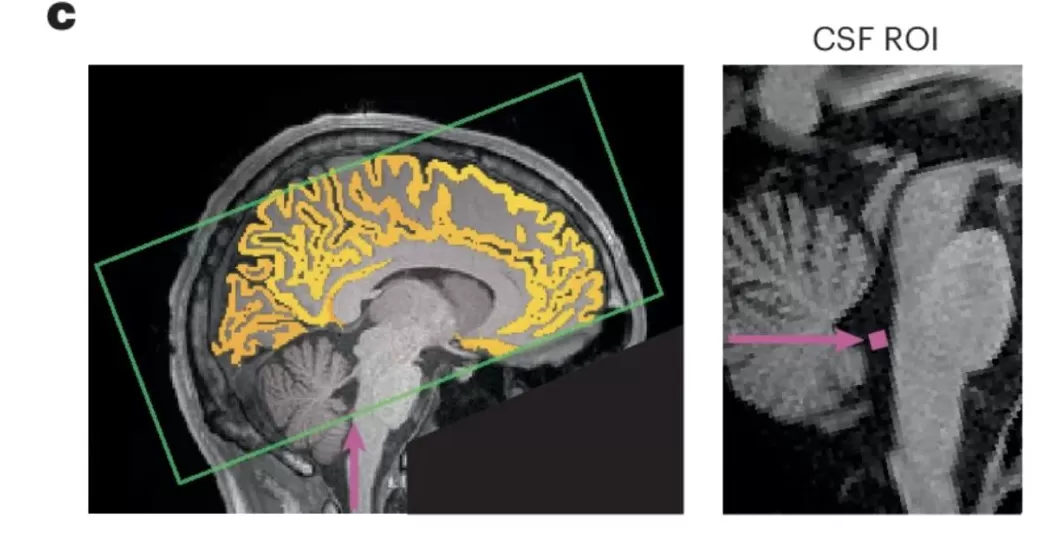

2025年10月发表在《自然神经科学》杂志上的一篇研究指出,熬夜后的注意力不集中,可能是因为你的大脑正在给自己「洗澡」[1]。

脑科学界这几年有个新理论:大脑会在白天产生代谢废物,在睡眠时通过脑脊液不断冲刷、清除掉,从而让大脑再次恢复清洁。[1][2]

有趣的是,通过脑部MRI扫描发现:

每次注意力「断片」的前2秒,脑脊液会被冲出脑底;而注意力恢复后的1秒,又会被重新吸回大脑。

也就是说,你在发呆、走神的时候,大脑正在进行「紧急冲洗」。

图源:https://www.nature.com/articles/s41593-025-02098-8